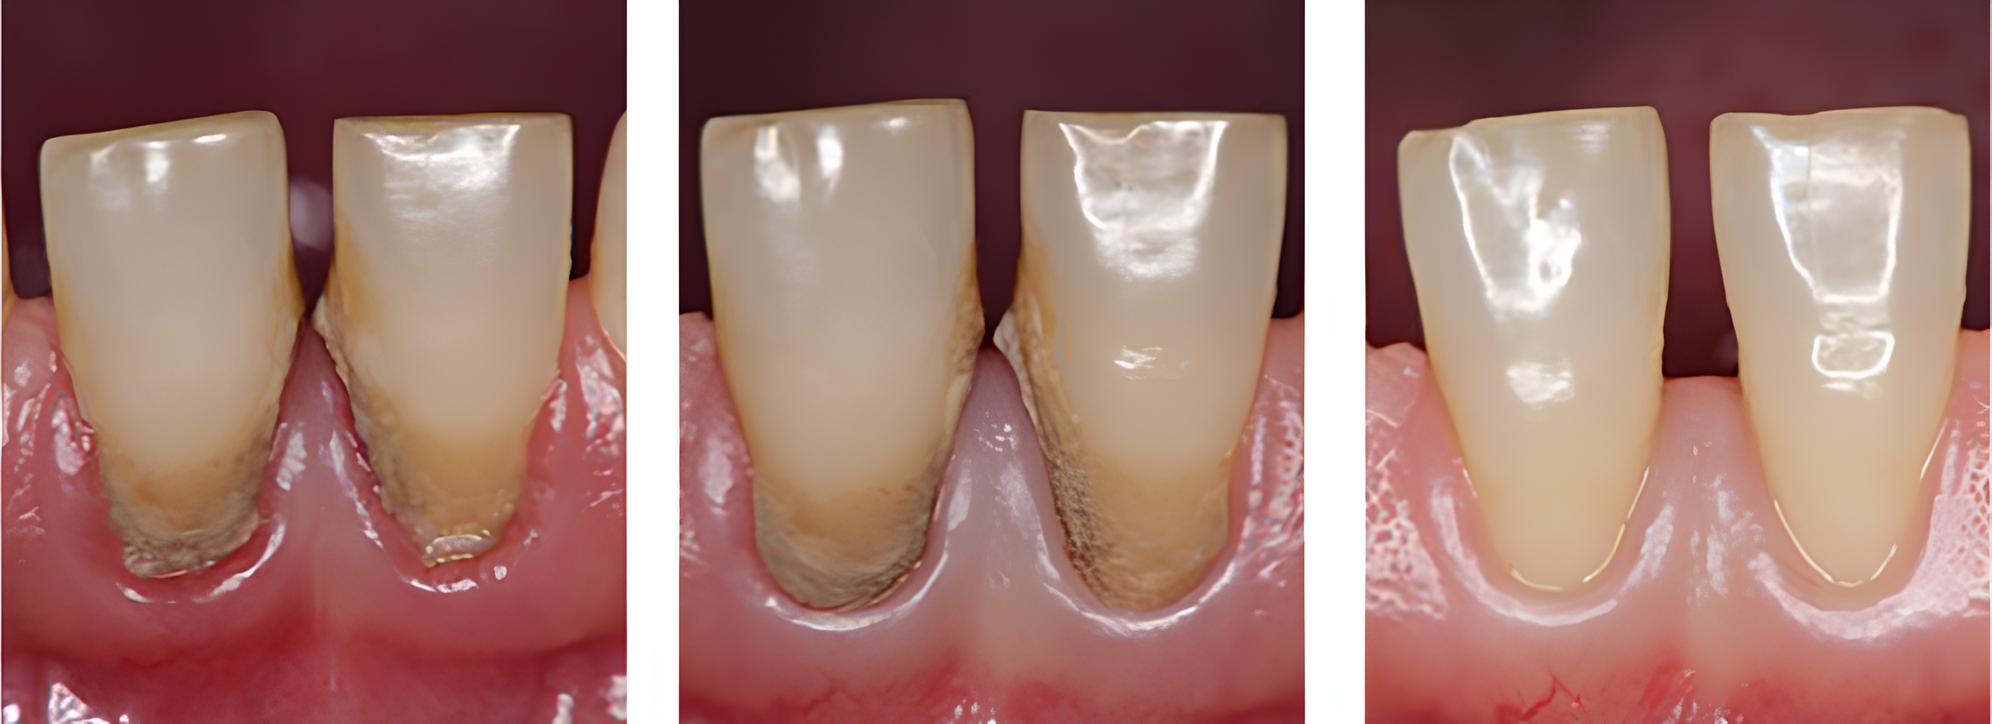

歯周病治療

術前

術中

術後

| 治療内容 | 歯磨き指導を行い、歯肉の発赤・腫脹が改善されたため歯石除去を行った |

|---|---|

| 治療期間・回数 | 1カ月・2回 |

| 費用 | 保険適用となります |

| リスク・副作用 |

|